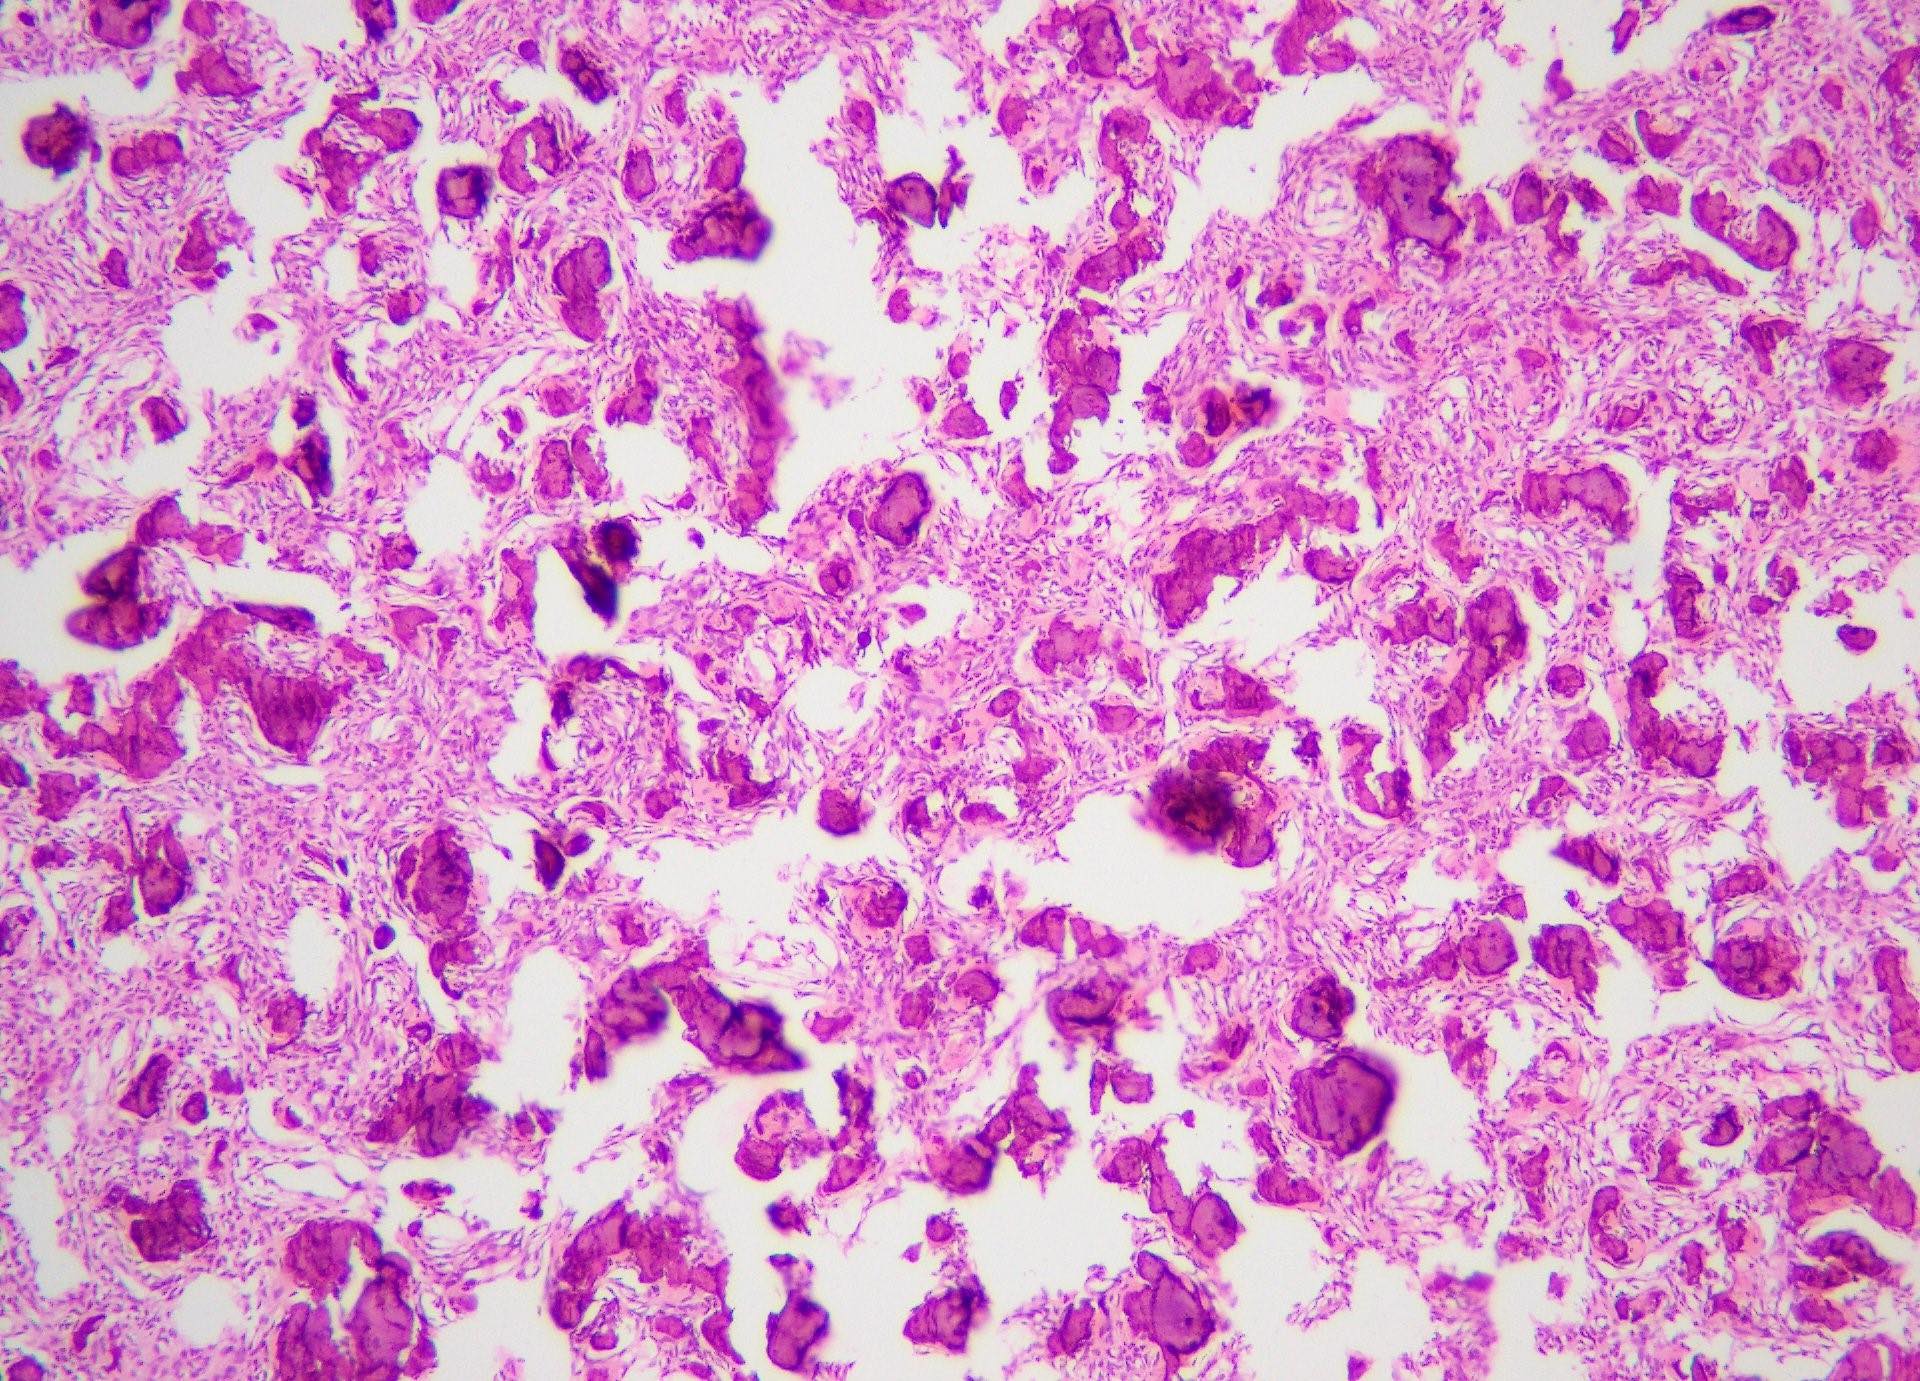

Microscopic (histologic) images

Contributed by Saira Javeed, M.B.B.S., M.Phil., Kelly Magliocca, D.D.S., M.P.H. and Molly Housley Smith, D.M.D.

- Well defined lesion; may have thin fibrous capsule

- Well demarcated margin from surrounding normal bone

- Lesion consists of variable proportion of fibrous and mineralized tissue, more heavily mineralized centrally; it shows variation in the amount and type of mineralization, even within a single lesion

- Osteoblastic rimming of bone trabeculae is frequent (J Stomatol Oral Maxillofac Surg 2022;123:364)

- Stroma is fibroblastic with areas of hypercellularity and nuclear hyperchromasia

- No significant atypia and mitoses are infrequent (Head Neck Pathol 2020;14:70)

- Woven to lamellar bone, osteoid and dense acellular or paucicellular basophilic rounded cementum-like calcifications may all be present (Head Neck Pathol 2020;14:70)

- Bony trabeculae may form thick anastomosing strands or fuse into large sheets centrally

- Areas resembling cemento-ossifying fibroma may be seen in psammomatoid and trabecular ossifying fibroma; cemento-ossifying fibroma may contain ossicles like psammomatoid ossifying fibroma